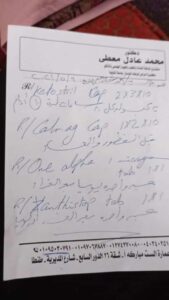

وكشفت شقيقة المصاب أنها عرضت كافة التقارير الطبية والأشعة والفحوصات الطبية على استشاريين في جراحات الرمد والمخ والأعصاب والأنف والأذن، حيث أكدوا أن حالته نادرة ومتأخرة صحياً بسبب توغل الفطر الأسود، وتسببه في تلف الأنسجة بالعين وفكي الفم والعينين، ما قد يتسبب فى وفاته في حال وصول الفطر لخلايا المخ.

وحول حالة المصاب، أوضح وكيل وزارة الصحة أنه تم الإطلاع على كل التقارير الطبية، حيث تبين وجود كسر بالعين اليمنى، وسيتم التنسيق مع مستشفى الرمد الجامعي بجامعة طنطا لاستقبال الحالة وعلاجها، وتوفير الرعاية الصحية الكاملة خلال الفترة المقبلة